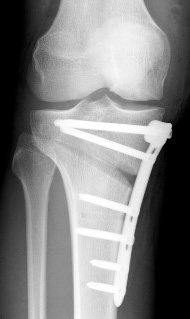

Figure 2. Arrows indicate the load distribution before (left) and after (center) the procedure (medial open wedge osteotomy with locked plate osteosynthesis)(right). Used under CC BY-SA 3.0 de license. Source. Image (right) by J Lengerke.

A wedge-shaped cut (see Figure 1) is made in the top of the tibia to change the alignment of the knee by shifting the weight/loading of the arthritic part of the joint to the healthier part (see Figure 2) [12]. It is mostly performed for varus deformities, less commonly for valgus deformities [13]. Preoperative planning using imaging helps surgeons to calculate the size of the wedge/osteotomy needed to correct the weight-bearing axis (see Figure 3). For best results, it is critical that correct alignment is achieved [14]. There is controversy around what constitutes the ideal mechanical alignment but generally the recommended alignment range is between 2° and 6° of mechanical valgus [15].